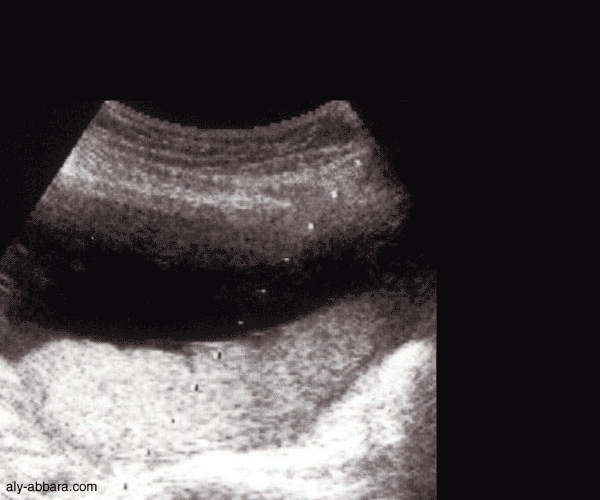

Amniocentèse

sous contrôle échographique

(prélèvement du liquide amniotique par ponction de la cavité amniotique)